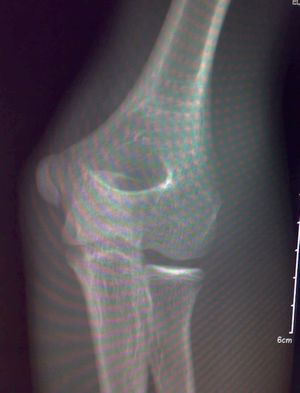

影像所见:左肱骨远端隐约可见自外上髁向髁间走行不规则骨质透亮线,侧位显示肱骨前线欠光整。未见脱位征象。骨骺发育未见异常。

印象:左肱骨远端骨折不除外。

建议:斜位投照或ct。

是内上髁正常存留骺影

加照对侧,感觉肱骨外上髁上方内侧骨骺旁显示低密度负影。

是正常骨骺,必要时加照对侧。

是内上髁正常存留骺影,支持